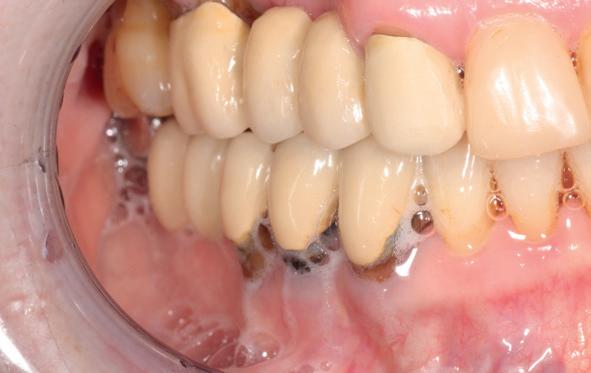

In de prothetische fase (zie foto’s) is in de bovenkaak gebruikgemaakt van verschroefde zirconia bruggen, die enkel buccaal zijn opgebakken. Deze bruggen zijn verlijmd op individuele, geanguleerde titanium abutments. In de onderkaak is een verschroefde kunststofbrug op een titaniumbasis (wrap-around) gemaakt. Voor deze combinatie is gekozen vanwege een minder hinderlijk tikkend geluid bij functie en kleinere kans op breuk van de keramiek. Een nadeel is verhoogde slijtage van de kunststof elementen, maar deze zijn in de jaren later eenvoudig te vervangen op de bestaande brug. Ondanks alle digitale mogelijkheden is de afdruk en registratiefase analoog uitgevoerd, omdat in ervaring van de behandelaren dit bij deze totale rehabilitaties op implantaten nog altijd de grootste precisie oplevert. Er is afgedrukt met impregum in individuele lepels en de pasvorm is gecontroleerd met rigide duralay bars. De relatie wordt vastgelegd zoals bij een volledige prothese met waswallen en pijlpuntregistratie. De opstelling in was wordt gepast en laatste correcties worden gemaakt in samenspraak met de patiënt, de restauratieve tandarts en de tandtechnicus. Na het vastzetten van de suprastructuren worden de schroefgaten afgesloten met composiet.

10. In de bovenkaak is gekozen voor 3 zirconium bruggen; in de onderkaak is gekozen voor een wrap-around met titanium

core.

11. In de bovenkaak is keramiek gebruikt en in de onderkaak kunststof (behandeling is

in de zes maanden bij de mondhygiënist voor peri-implant reiniging, pocketmetingen, mondhygiëne instructies en controles. De AirFlow wordt daarbij standaard gebruikt. Verder wordt de patiënt na één, drie en zes jaar gezien voor controle van de suprastructuren door de restauratieve tandarts. Uit de röntgenfoto’s kan afgeleid worden dat het botniveau gelijk blijft over tijd. Klinisch ziet de situatie er infectievrij uit; de patiënt onderhoudt het zelf netjes met ragertjes, een elektrische tandenborstel als ook de Waterpik.